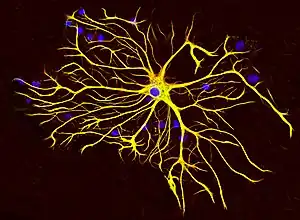

The reason for increased deposition of Aβ in sporadic CAA is still unclear with both increased production of the peptide and abnormal clearance having been proposed as potential causes.[13] Under normal physiology Aβ is cleared from the brain by four pathways: (1) endocytosis by astrocytes and microglial cells, (2) enzymatic degradation by neprilysin or insulysin (3) cleared by way of the blood–brain barrier or (4) drained along periarterial spaces. Abnormalities in each of these identified clearance pathways have been linked to CAA.[14][15]